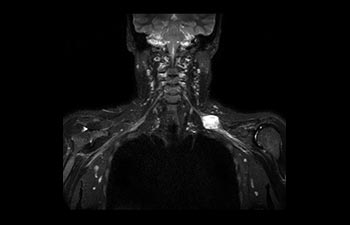

Plexus brachialis

Läsion am Plexus brachialis